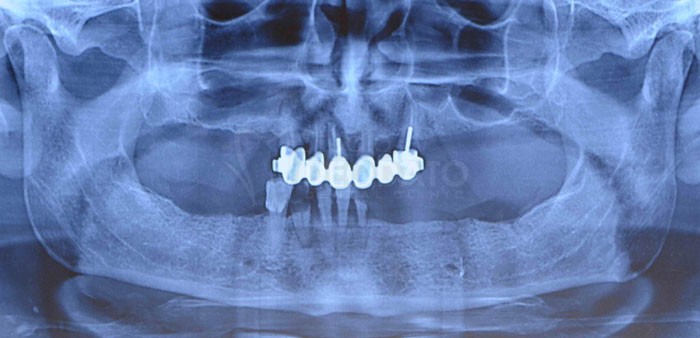

Rx-OPT di controllo finale